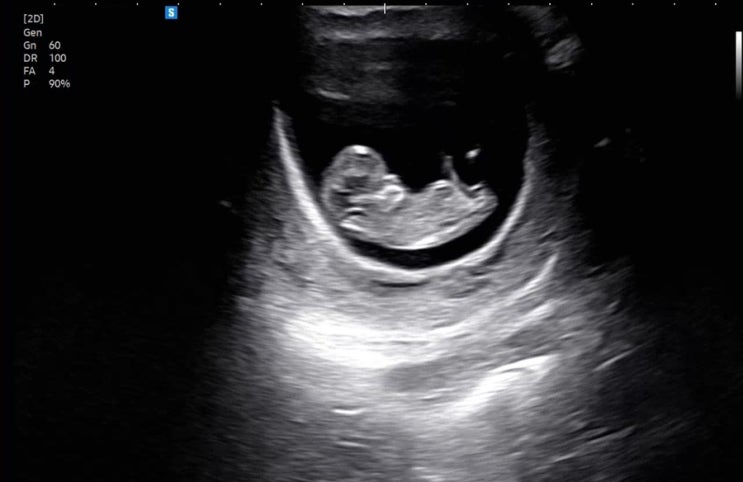

임신 11,12주차 / 두통과 어지러움 그리고 난리난 피부

11주, 12주차 증상 - 두통 특히나 밤에 머리가 깨질듯이 아파옴 - 어지러움 기립성 어지러움..(?) 앉아있다...